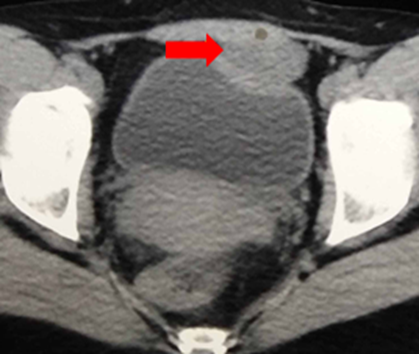

·         Computed Tomography (CT): A CT scan provides detailed information about the cyst's size, location, and relationship to surrounding structures. It can also help identify complications like infection or abscess formation.